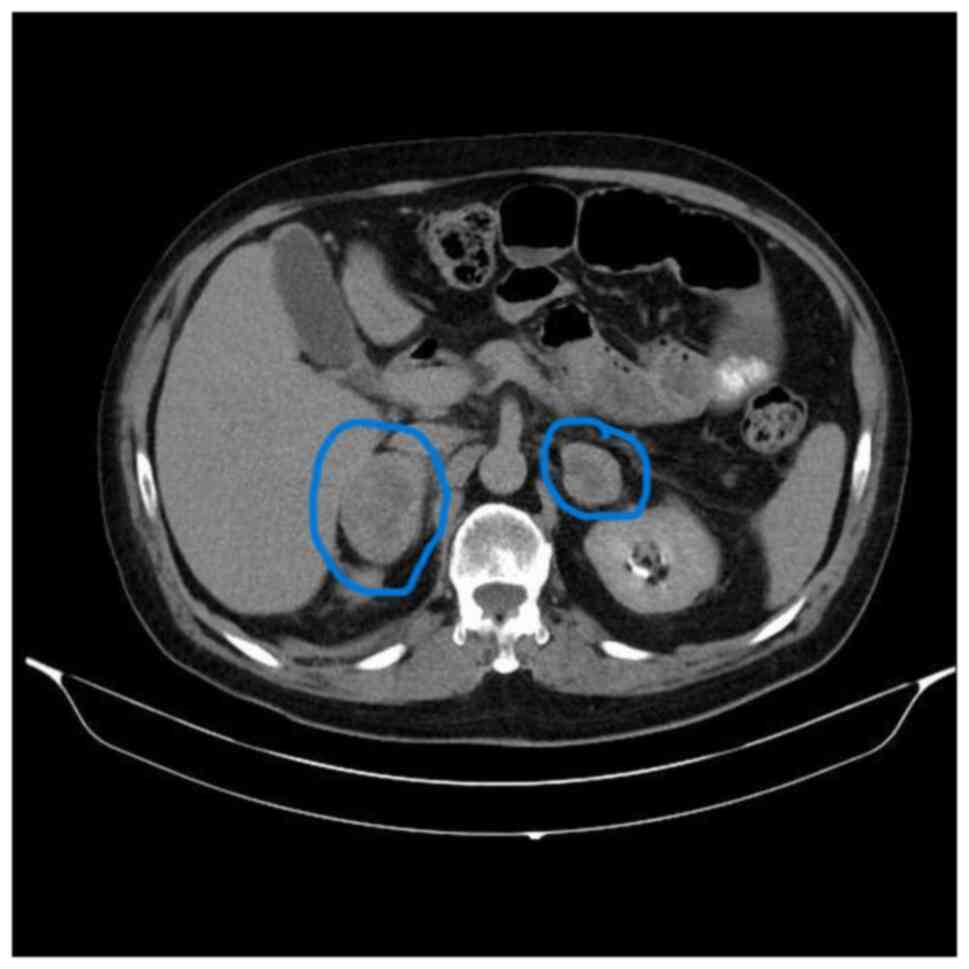

In August 2019, the patient was admitted to the emergency department of Uludag University Hospital (Bursa, Türkiye) with abdominal pain and diagnosed with acute pancreatitis. The patient was transferred to the intensive care unit and intubated due to acute respiratory distress syndrome. The patient was extubated and discharged two months later. At that time, positron emission tomography-computed tomography (PET-CT) showed local regression. However, during follow-up, in March 2021, CT revealed newly developed heterogeneous contrasting nodular lesions measuring 5×3 cm in the right and 4×4.5 cm in the left adrenal gland (Fig. 1). Due to multiple progressive lesions, the biopsied specimen was histologically processed. The tissue samples were fixed in 10% neutral-buffered formalin for 24 h and the tissue treatment for staining was followed as specified above. The H&E staining process involved incubating the sections in hematoxylin for 5 min, followed by eosin for 2 min. The sections were then assessed using a light microscope. The same histopathology protocol was used for all H&E stainings. Malignant melanoma metastasis (Figs. S1 and S2) was confirmed by immunohistochemical staining for anti-melanosome (HMB45; 1:100 dilution; cat. no. 790-4366; Roche Tissue Diagnostics). The same OptiView DAB IHC Detection Kit and visualization settings were used as specified earlier.

Axial CT scan demonstrating bilateral

adrenal metastases revealed heterogeneous, contrast-enhancing

nodular lesions measuring 5×3 cm in the right adrenal gland and

4×4.5 cm in the left adrenal gland (blue circles; May 2021).

Figure 1.

Axial CT scan demonstrating bilateral adrenal metastases revealed heterogeneous, contrast-enhancing nodular lesions measuring 5×3 cm in the right adrenal gland and 4×4.5 cm in the left adrenal gland (blue circles; May 2021).